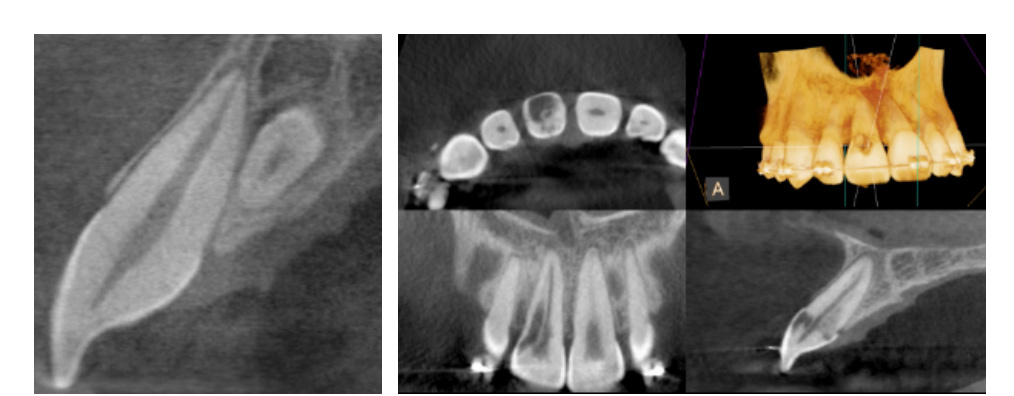

Cone beam computed tomography (CBCT) offers accurate and high quality 3-D representations of dental and facial structures. This enables our endodontists to more precisely diagnose an underlying problem, detect unforeseen defects, and minimize the need for exploratory procedures. CBCT facilitates more effective care and more consistent successful outcomes.

Clinical applications of CBCT technology in endodontics include the following:

Occasionally, dental defects or pathology that deem a tooth non-restorable will be revealed on a CBCT scan. If this happens, the endodontist will advise you that the tooth cannot be saved.

(Pictures of missed canal, vertical root fracture, extra tooth, and resorption)